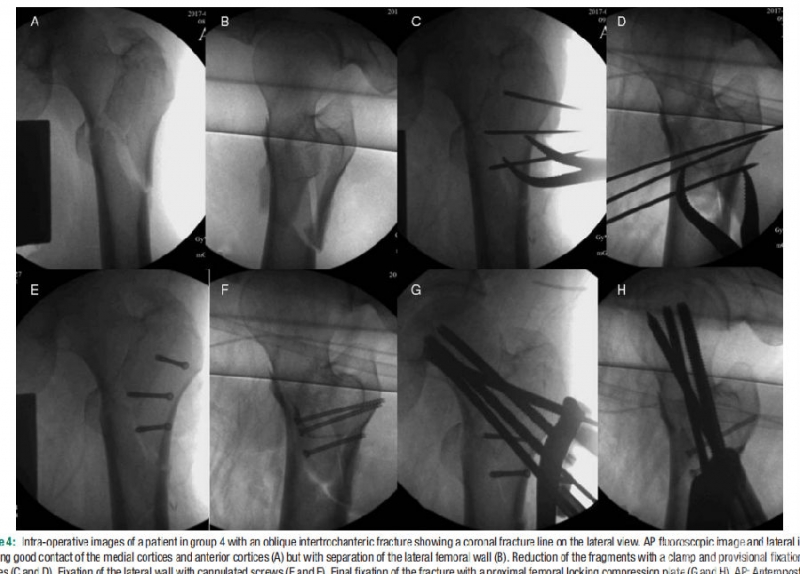

图2. 外侧壁劈裂型骨折的影像学特点及复位方法

根据骨折影像学特点,难复性骨折可分为四种类型:I型为断端交锁型,复位的方法是适当放松牵引,放松髂腰肌,利用骨膜剥离子顶压骨折块等;II型为股骨干后沉型,复位的方法是设法抬起股骨干;III型为内侧壁或外侧壁劈裂型,复位的方法是用复位钳钳夹骨折块、钛缆捆扎等;IV型为转子下粉碎型,复位方法为综合运用骨钩、复位钳、股骨干提起等复位技术。

结论:难复性股骨转子间骨折的发生率约为19.3%。根据骨折的影像学特点,可分为断端交锁型、股骨干后沉型、内侧壁或外侧壁劈裂型、转子下粉碎型四种类型。复位技术包括适当放松牵引、松解髂腰肌、骨钩牵引、复位钳钳夹、抬高股骨干等。